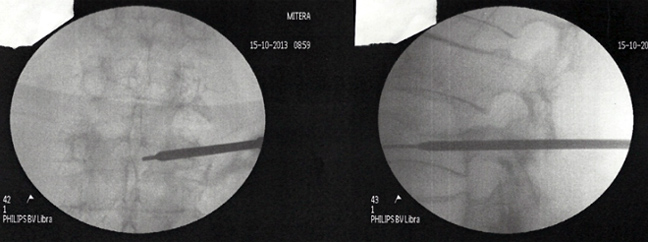

Η λύση αυτή ονομάζεται κυφοπλαστική. Χωρίς ανοικτή εγχείρηση, μέσω μίας χοντρής βελόνας (trocard) και παρακολουθώντας τη διαδρομή μέσω ακτινολογικής τηλεόρασης, εισάγεται μέσα στο σώμα του σπασμένου σπονδύλου ένα μπαλονάκι που φουσκώνει με νερό. Αναλόγως της πίεσης που ασκείται, ο σπόνδυλος διορθώνεται.

Στην κοιλότητα που δημιουργείται εισάγεται ακρυλικό τσιμέντο που όταν πήξει μετά μερικά λεπτά, καθιστά σταθερό και πάλι τον σπόνδυλο.